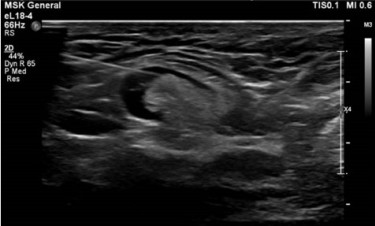

Tracking vaccine responses in lymphoid organs

We use ultrasound-guided lymph node fine needle aspirations to monitor pneumococcal vaccine responses within draining lymph nodes. Our studies assess how these responses that generate immune memory vary by vaccine platform, aging, and HIV infection. Immune profiling includes antigen-specific B and T cells using spectral flow cytometry, enabling comparisons between lymph nodes and peripheral blood to better understand localized and systemic vaccine-induced immunity.